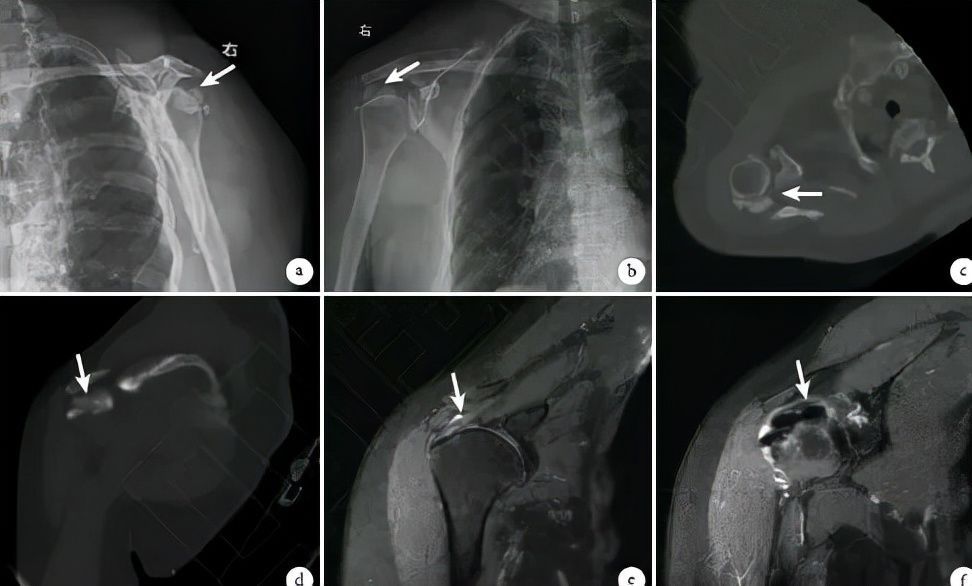

文章插图

白色箭头处为肌腱钙化灶

江主任安抚好王阿姨的情绪后,详细向王阿姨询问了病史并翻阅了之前的病历,做了相关的查体后,对病情已经大概了解——王阿姨7个月前已经在外院诊断为肩周炎,刚开始予以吃药、康复等保守治疗,随着病情的发展,保守治疗逐渐失效。

江主任迅速给王阿姨安排了肩关节 X 光片及核磁检查。慢慢地,一个肩关节隐形杀手的真面目逐渐暴露在大家面前——肩袖钙化性肌炎。